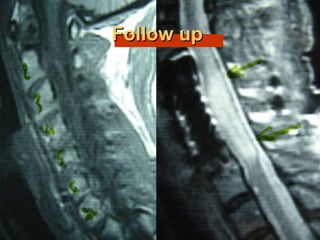

33rdrd

casecase

Ma. Pal.

F 56

Unknown origin

Symptoms

Neurologic deficit

Pain

Low fever

56

Follow upFollow up

Pus culture

(staphylococous aureous)

Antibiotics

i-v for 2 mts

orally for 6 mts

Complete neurologic recovery